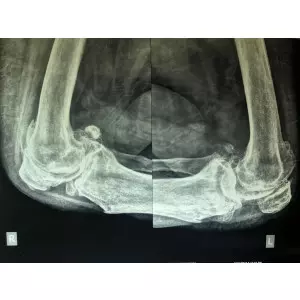

Details of Single Sitting Total Hip And Knee Replacement F/75 Obese